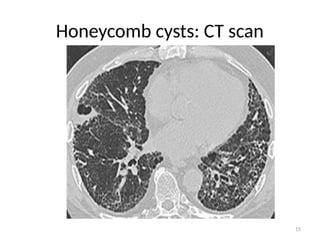

• Honey combed cysts

– Due to widespread fibrosis:

» Small cystic spaces form with irregularly thickened walls

Honeycomb cysts: CT scan